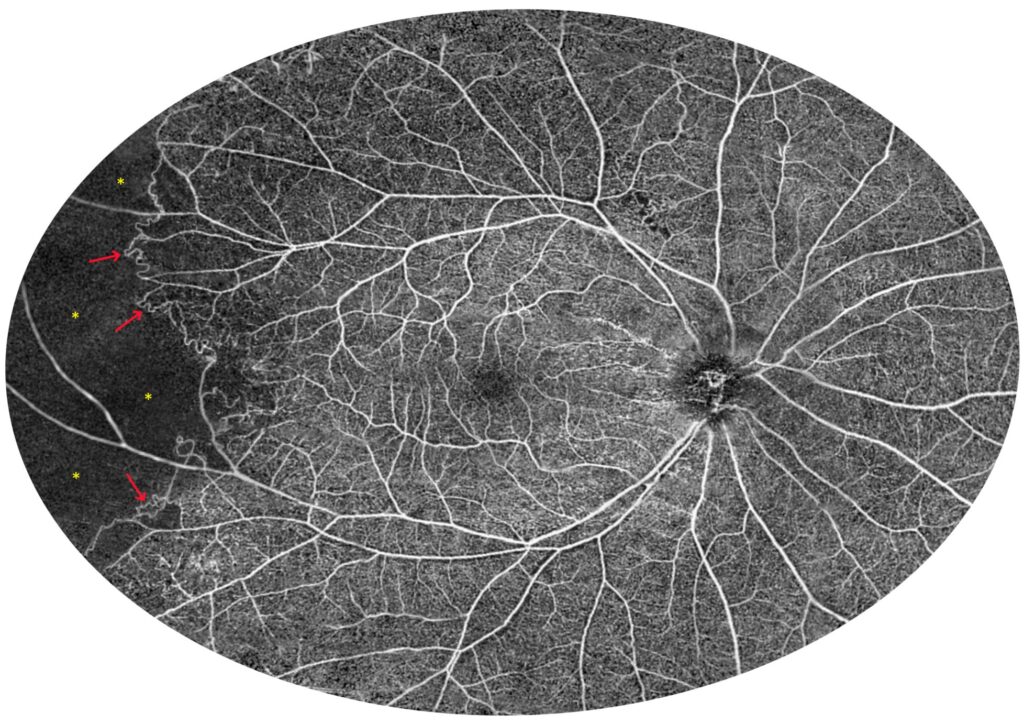

The next two cases present patients with proliferative DR. Figure 12 shows a 6 × 6 mm scan of the macula. It presents an enlargement of the foveal avascular zone and small areas of non-perfusion around it. It does not provide any other retinal or flow information. In contrast, the 22 mm UWF scan shows extensive zones of non-perfusion (asterisks) in the periphery and vascular proliferation (arrows), in addition to the above-mentioned changes in the centre. Thus, it indicates an urgent need for extended treatment. Figure 13 relates the 22 mm UWF angio-OCT scan to the wide-angle fluorescein angiography (FA) mosaic. Both examinations reveal vascular proliferation (red arrow), capillary dropout (blue arrow), and non-perfusion zones (asterisk). However, angio-OCT shows vascular structures more clearly due to the lack of background fluorescence, as well as the staining of other lesions.

Figure 12. Proliferative diabetic retinopathy (female, age 54). (A). Colour fundus photograph and 6 × 6 mm OCT angiography. (B). UWF OCT angiography from a 22 mm wide area. The asterisks indicate non-perfusion zones and the arrows point to vascular proliferation. (C). UWF OCT scan of the posterior pole.

Figure 13. Proliferative diabetic retinopathy (male, age 37). (A) A wide-angle fluorescein angiography mosaic. (B) UWF OCT angiography covering a 22 mm wide area. The red arrows point at the vascular proliferation, whereas the blue arrows indicate capillary dropout. The asterisks show non-perfusion zones.